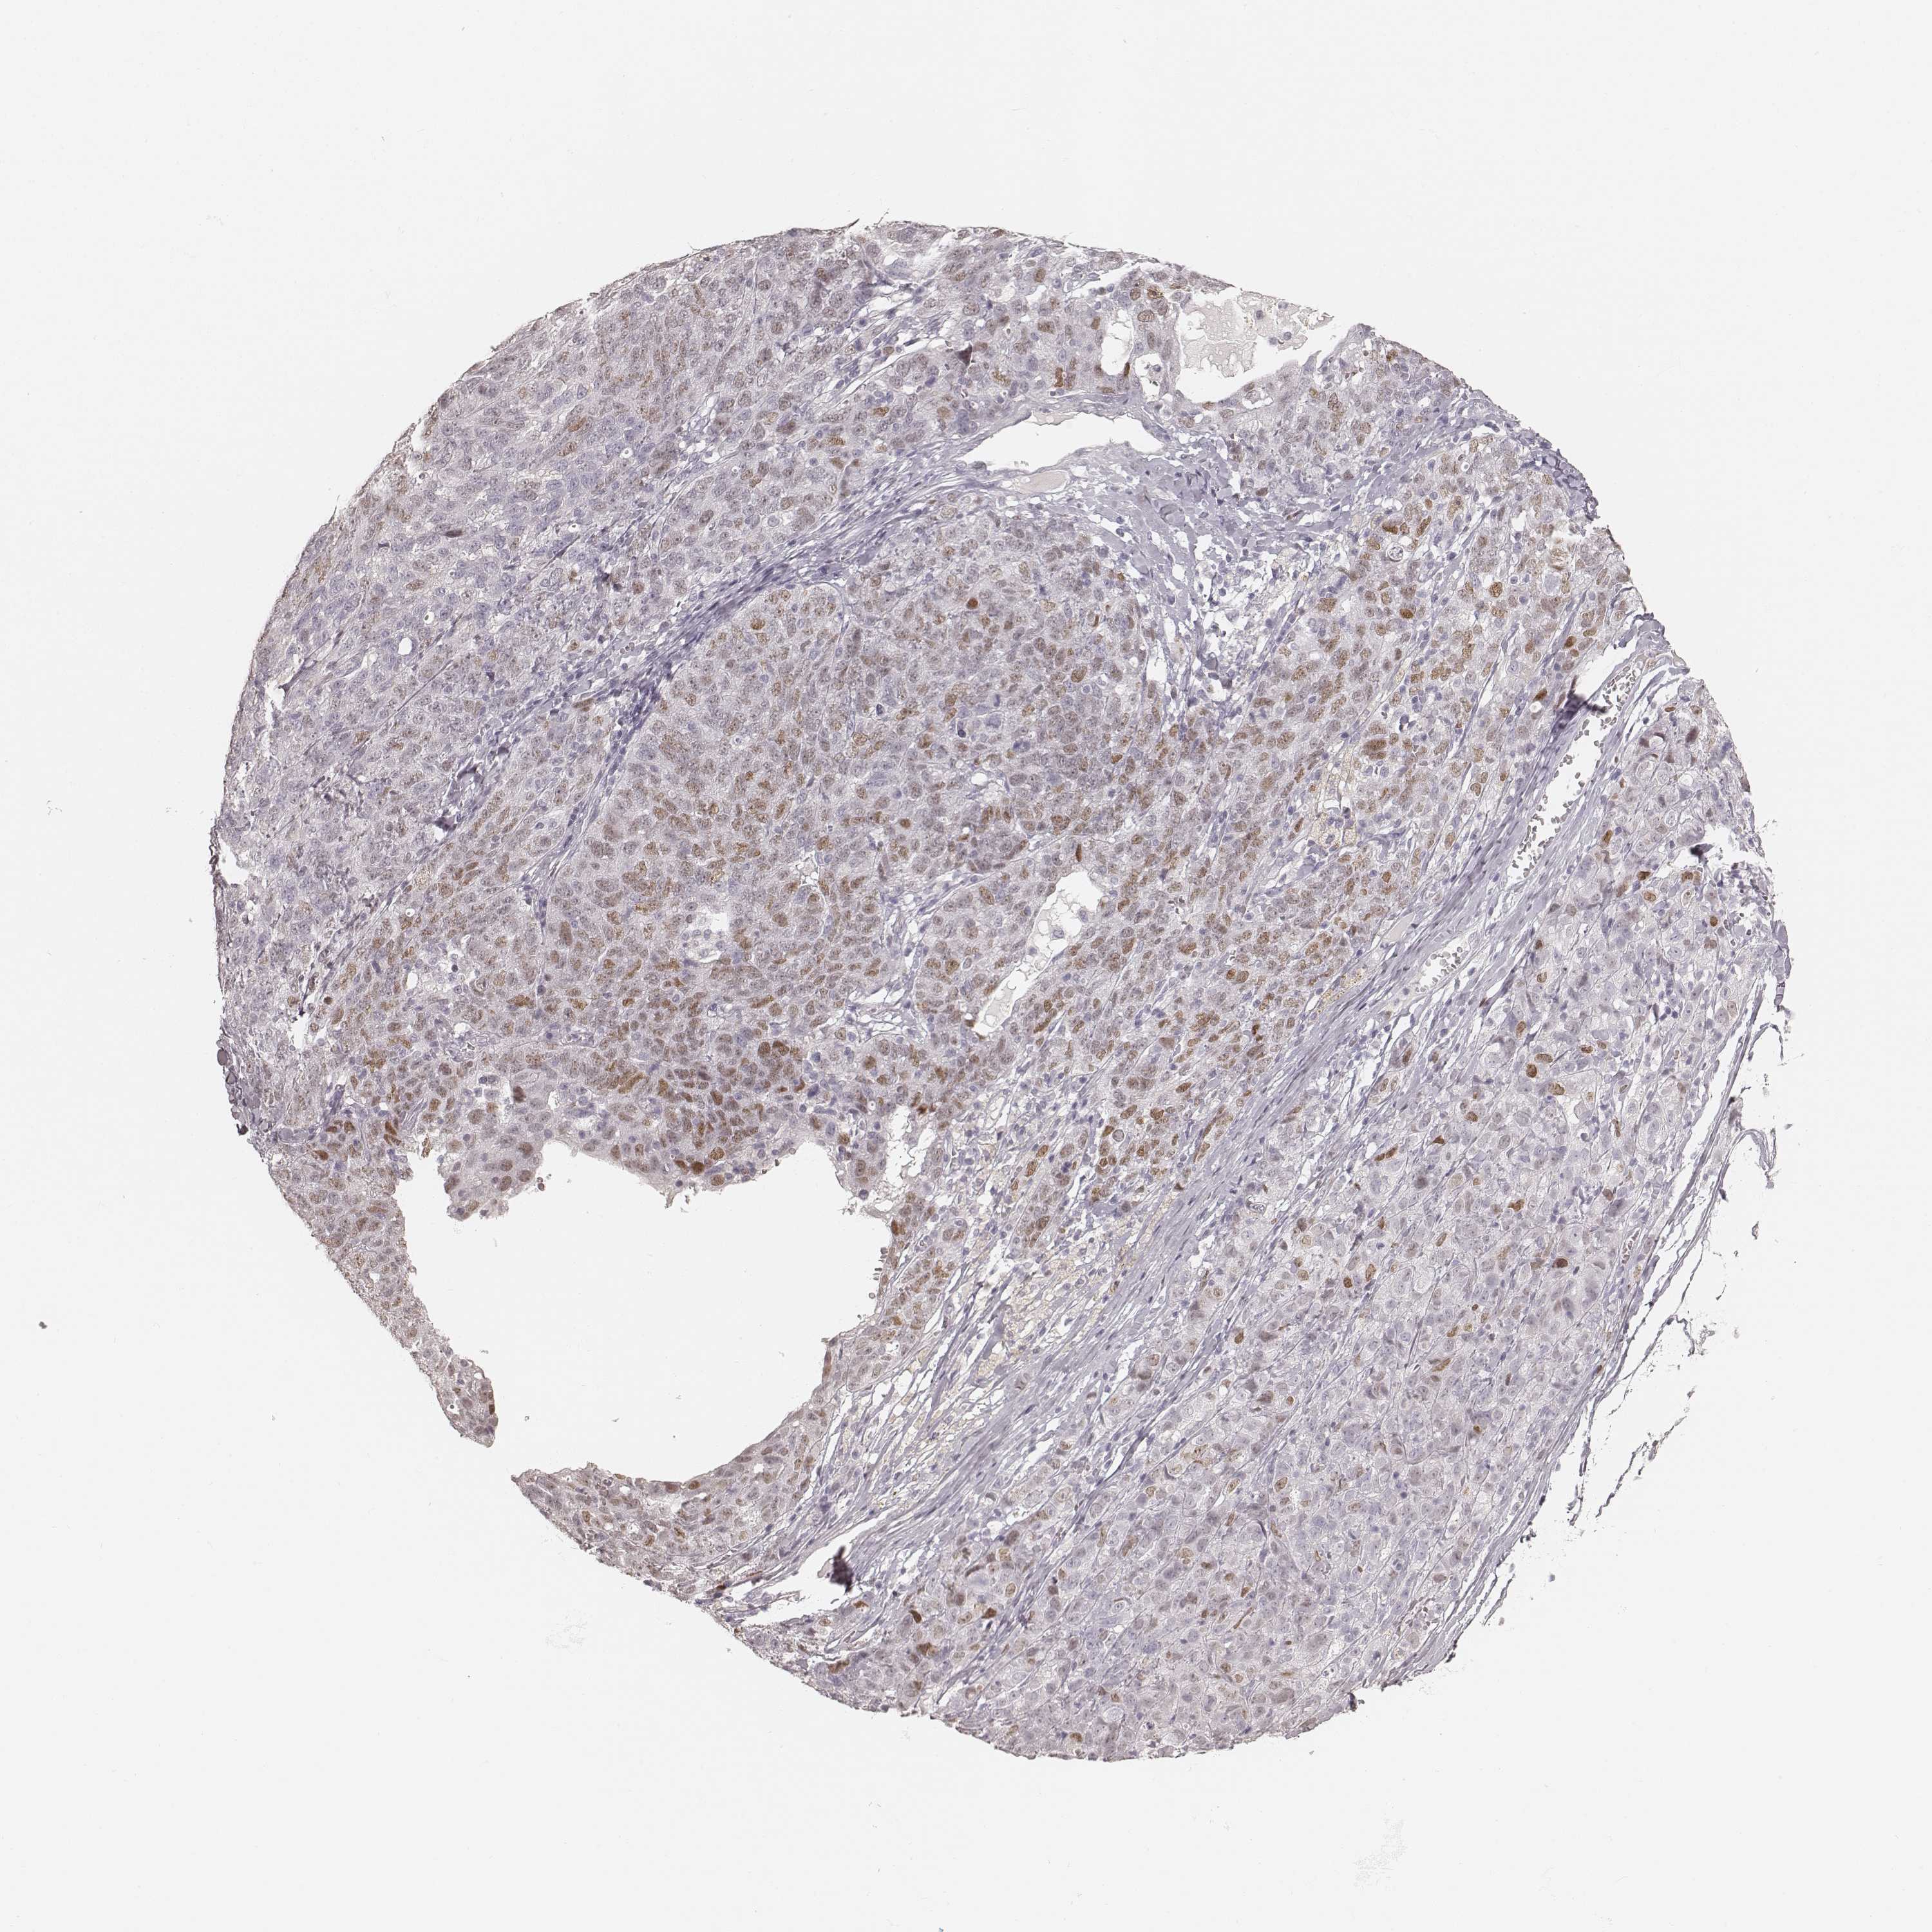

OVARIAN CANCER - Protein expressioni

A mouse-over function shows sample information and annotation data. Click on an image to view it in a full screen mode. Samples can be filtered based on level of antibody staining by selecting one or several of the following categories: high, medium, low and not detected. The assay and annotation is described here.

Note that samples used for immunohistochemistry by the Human Protein Atlas do not correspond to samples in the TCGA dataset.

Antibody stainingi

Antibody staining in the annotated cell types in the current human tissue is reported as not detected, low, medium, or high, based on conventional immunohistochemistry profiling in selected tissues. This score is based on the combination of the staining intensity and fraction of stained cells.

Each image is clickable and will lead to virtual microscopy that enables deeper exploration of all samples and also displays staining intensity scores, fraction scores and subcellular localization as well as patient and tissue information for each sample.

Antibody HPA043987

Cystadenocarcinoma, serous, NOS

Cystadenocarcinoma, mucinous, NOS

Carcinoma, endometroid